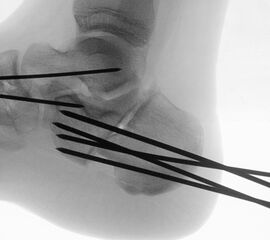

Zusätzlich schränken Wachstumsfugen die Wahl der Osteosynthese ein. Eine die Fuge kreuzende Osteosynthese ist ausschließlich mit Kirschner-Drähten möglich (Abb. 3).

Abb. 3 a-j: Beispiel einer Calcaneusverschiebeosteotomie mit offenen Wachstumsfugen und der entsprechenden Osteosynthese mit Kirschner Drähten. Lokalisation der Osteotomie (a), Lage der Fräse (b-d), Drahtlage mehrere Ansichten (e-h), Heilung der Osteotomie 4 Wochen postoperativ und Entfernung der Drähte (i-j).

Zum Lesen der Bildbeschreibung und zur Vollansicht bitte die Bilder anklicken. Bilder: A. Helmers.

Calcaneus-Osteotomie

Die minimalinvasive Calcaneusverschiebeosteotomie bietet eindeutige Vorteile gegenüber dem offenen Verfahren, sodass wir bei Kindern und Jugendlichen nahezu keine offene Verschiebeosteotomie mehr durchführen. Am Calcaneus liegt die offene Wachstumsfuge dorsal. Bei der Durchführung müssen Schenkel der V-förmigen Osteotomie daher etwas steiler angelegt werden, in einem stumpfen Winkel (siehe Abb. 3 a-j). Für die Osteotomie liegen unsere Patienten auf dem Rücken und der BV wird für die exakte Seitaufnahme eingestellt. Der Fuß lagert auf einem hohen OP-Kissen und die Osteotomie kann bequem mit einem langen Kirschner-Draht und einem sterilen Stift angezeichnet werden (Abb. 15).